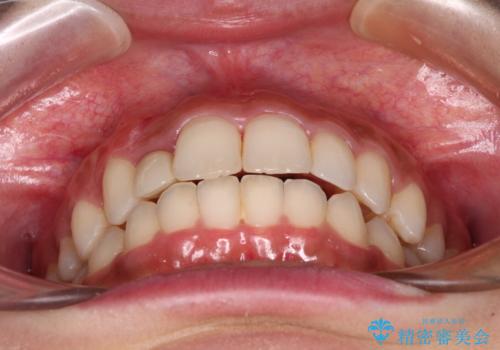

抜けてしまうと言われた前歯 インビザラインによる矯正治療

- 上下前歯のデコボコを気にして来院された患者様です。

前歯のセラミックが装着されている歯は、歯根が短くなっており、他院では抜けてしまうので矯正はできないと言われていたようです。

患者様と相談し、抜けてしまった場合にはインプラントあるいはブリッジによる補綴治療が必要となることを確認し、極力歯根に負担のかからないような仕上がりで治療を進めて行くこととしました。

デコボコを解消には、IPR(歯と歯の間を削る)をメインに歯列排列を設計し、インビザラインにて矯正治療を行うこととしました。

レントゲン写真上では、矯正治療前後で歯根長さに大きな違いはなく、抜歯を回避することができました。

上顎内側に転位している前から2番目の歯は移動が難しく、無理矢理歯根全体を動かそうと設計すると、歯肉退縮・歯髄壊死・歯根吸収といった危険性が増すため、無難なゴールにて治療を終えることとなりました。